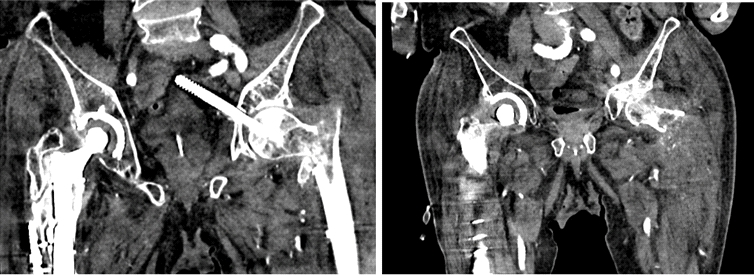

一名 85 岁男性因左股骨转子间骨折接受了短头髓钉固定术。跌倒后,检查显示头髓螺钉从内侧上移位到盆腔中。血管造影显示螺钉尖端位于髂骨分叉处 2 厘米以内,没有出血或内脏损伤的证据。

再次外伤后,拉力螺钉上内侧移位